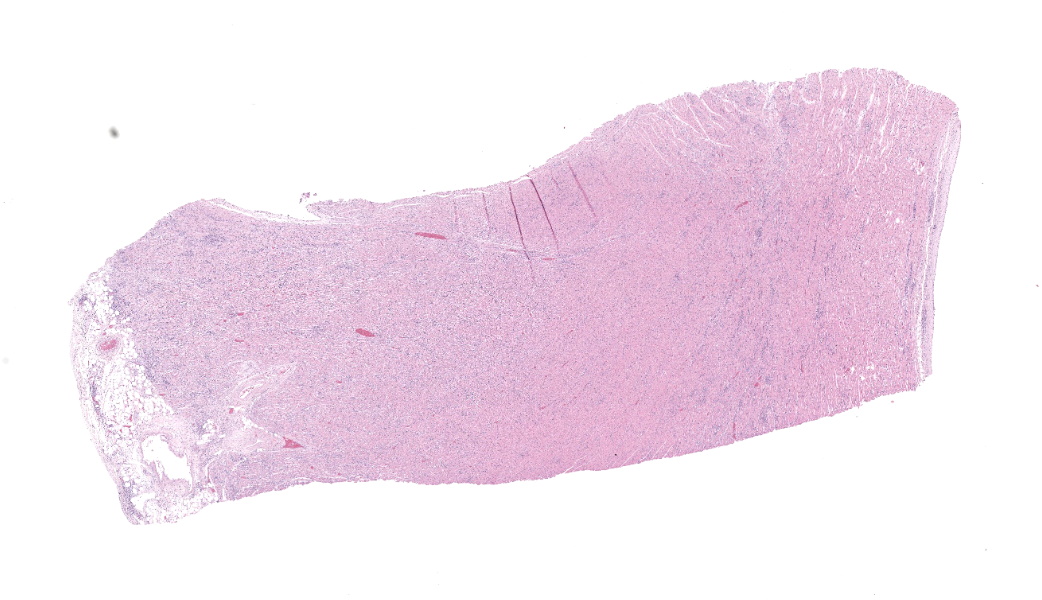

Expanding and infiltrating all layers of the heart, with the greatest severity in the myocardium, are large numbers of plasma cells, lymphocytes, and macrophages. Cardiomyocytes in areas of inflammation are multifocally hypereosinophilic, shrunken, and have striation loss with fragmented to absent nuclei (necrosis). There is mild, multifocal, interstitial fibrosis often associated with cardiomyocyte degeneration and inflammation. Throughout the myocardium, there are occasional cardiomyocytes that contain intrasarcoplasmic, variably sized (up to 100 μm in length) pseudocysts with numerous, 2-3 μm, round protozoal amastigotes.Contributor's Morphologic Diagnoses:

Heart: Severe, multifocal, chronic-active, lymphoplasmacytic and histiocytic pancarditis with intrasarcoplasmic pseudocysts containing amastigotesContributor's Comment:

Heart: Pancarditis, lymphoplasmacytic and histiocytic, subacute, multifocal to coalescing, marked, with numerous sarcoplasmic amastigotes.JPC Comment: